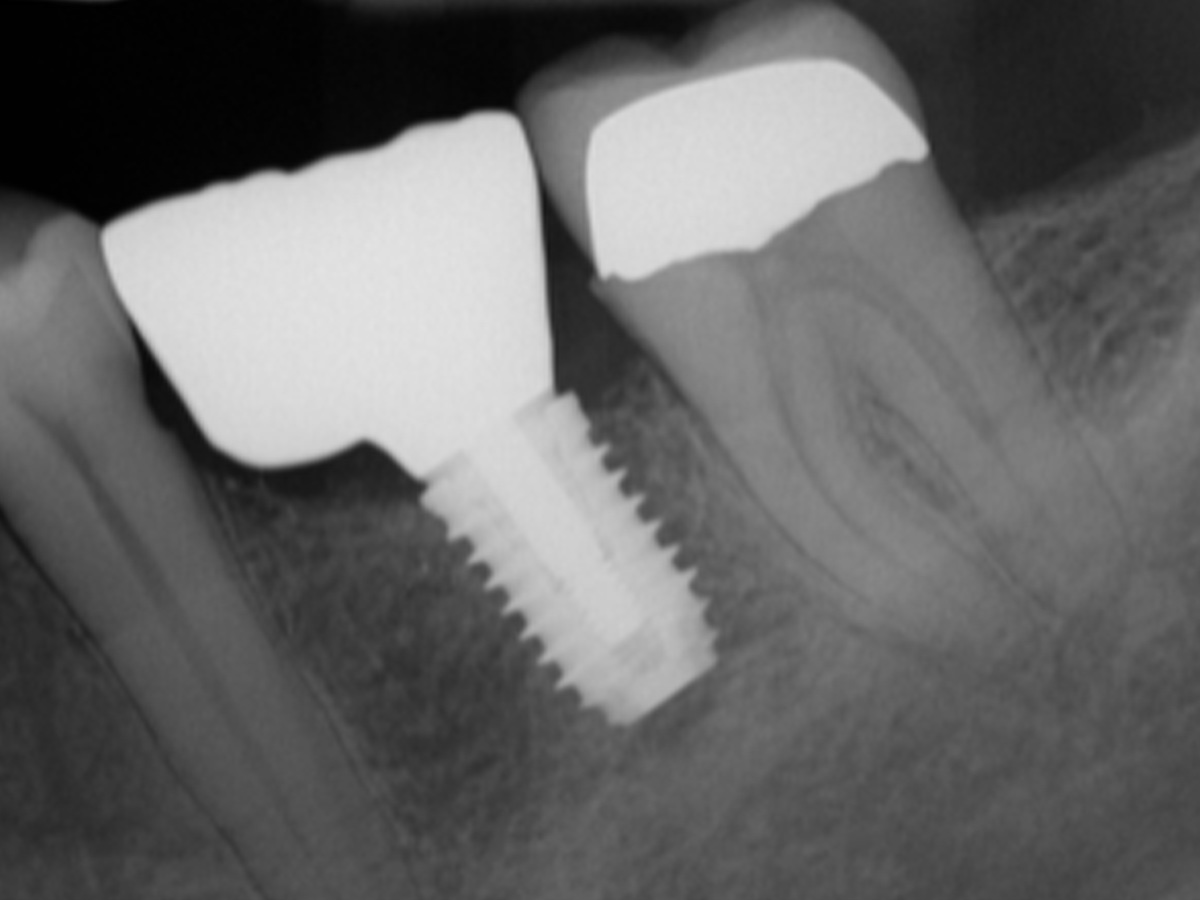

Bei den Abb. 10 und 11 handelt es sich um das Einzelzahnröntgen der Situation und das klinische Bild der implantatgetragenen Versorgung.

Abbildung 10

Augmentation nach fünf Monaten (röntgenologisch).

Abbildung 11

Endergebnis: Die implantatgetragene Versorgung.